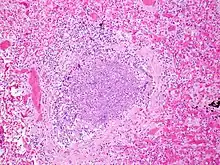

Bronchiolitis is most commonly caused by respiratory syncytial virus[7] (RSV, also known as human pneumovirus). Other agents that cause this illness include, but are not limited to, human metapneumovirus, influenza, parainfluenza, coronavirus, adenovirus, rhinovirus and mycoplasma.[12][13]

.jpg)